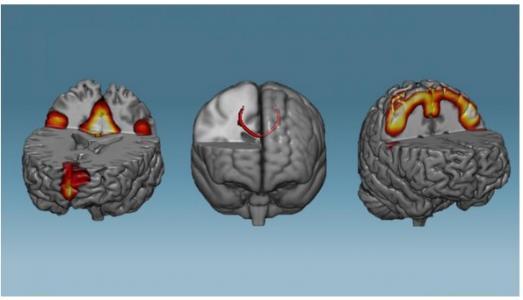

Ces scientifiques brésiliens ont mis au point une technique d’entraînement cérébral capable d’induire des modifications des réseaux de neurones… en moins d’une heure. En effet, une seule heure de ce neurofeedback induit une connectivité accrue des réseaux de neurones du réseau du mode par défaut (à gauche, sur visuel), des réseaux du corpus callosum ou corps calleux qui interconnecte les deux hémisphères cérébraux (au centre) et des zones sensorimotrices (à droite). Des données présentées dans la revue NeuroImage qui démontrent qu’il est possible d’entraîner son cerveau et, en pratique, d’accélérer la récupération cérébrale, après un accident vasculaire cérébral (AVC) par exemple.

Les chercheurs du D'Or Institute for Research and Education (IDOR, Rio de Janeiro), de l'Université fédérale de Rio et de l'Université Augusto Motta (Unisuam, Rio de Janeiro) démontrent que moins d’une heure d’entraînement cérébral avec neurofeedback renforce les connexions neuronales et la communication entre les zones du cerveau. Selon les auteurs, l'étude ouvre la voie à l'optimisation et au développement d'approches thérapeutiques post-AVC et dans la maladie de Parkinson, entre autres. « Nous savions que le cerveau présente une incroyable capacité d'adaptation, nommée « plasticité » mais nous n'étions pas certains de pouvoir obtenir et observer ces changements aussi rapidement. Comprendre comment nous pouvons optimiser le fonctionnement du cerveau est la clé du traitement des troubles neurologiques », conclut l’auteur principal, Theo. Marins, scientifique biomédical à l'IDOR.

Le neurofeedback est déjà documenté comme un moyen prometteur de réguler les zones cérébrales dysfonctionnelles associées à différents troubles, dont la douleur neuropathique chronique et la dépression. Ici, la technique de résonance magnétique permet aux patients « de prendre le contrôle » de leur propre activité cérébrale en temps réel. C’est ce que démontre cette expérience menée auprès de 36 sujets en bonne santé, ayant pour objectif d'augmenter l'activité des zones du cerveau impliquées dans les mouvements de la main. Au lieu de bouger réellement la main, les participants étaient invités à imaginer le mouvement mais restaient en situation de repos. 19 participants ont reçu le véritable entraînement cérébral par neurofeedback et les 17 autres participants ont reçu un « neurofeedback placebo ». Les chercheurs ont observé les réseaux neuronaux des participants immédiatement avant et après l'entraînement cérébral, qui a duré environ 30 minutes. L’analyse révèle qu’avec le neurofeedback,

- le corps calleux, le principal pont cérébral qui relie les hémisphères droit et gauche, présente une intégrité accrue et que le réseau neuronal contrôlant les mouvements du corps est renforcé ;

- tout le système cérébral apparaît plus robuste ;

- le neurofeedback montre également un impact positif sur le réseau en mode par défaut, un réseau cérébral altéré après un AVC, la maladie de Parkinson et la dépression ;